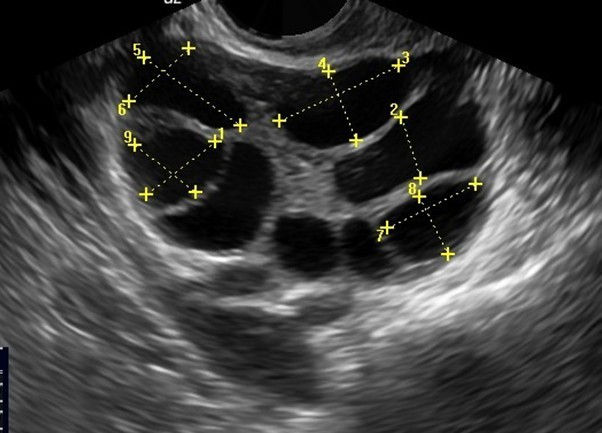

צוות מומחי הפוריות המנוסה של GI RIMON מספק טיפול חומל ומבוסס מדע לאבחון וטיפול בשורשי הפוריות הנשית